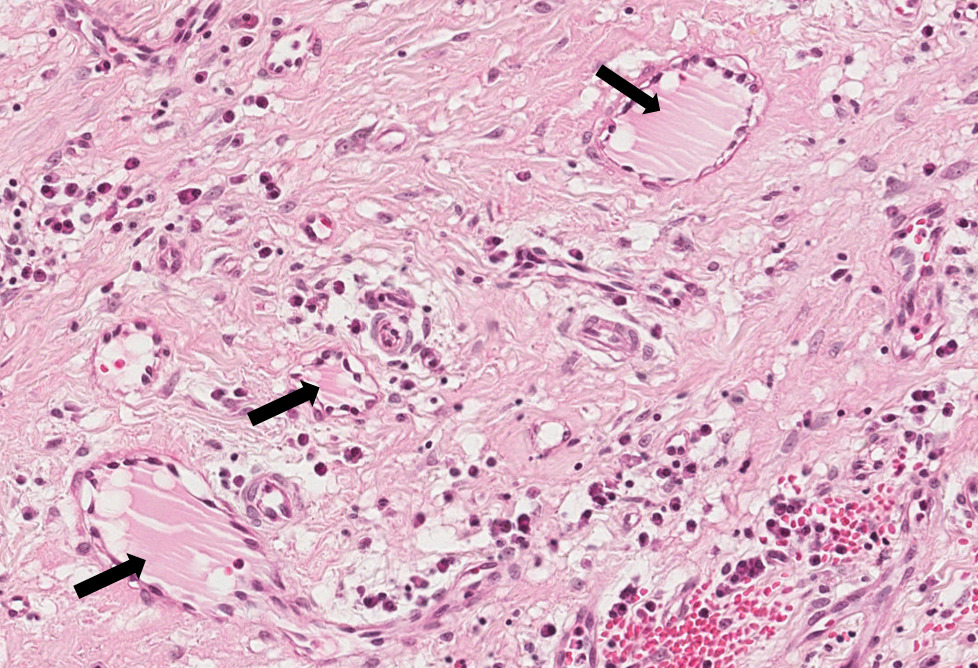

Observa-se uma área central onde encontram-se neutrófilos e piócitos caracterizando o pus. Em torno, circunscrevendo a supuração, observa-se tecido conjuntivo com processo inflamatório crônico e fibroplasia (cápsula). Na área de processo inflamatório crônico pode-se observar inúmeros linfócitos e plasmócitos. Alguns plasmócitos apresentam degeneração hialina (Corpúsculos de Russel-setas).

Abscesso Crônico